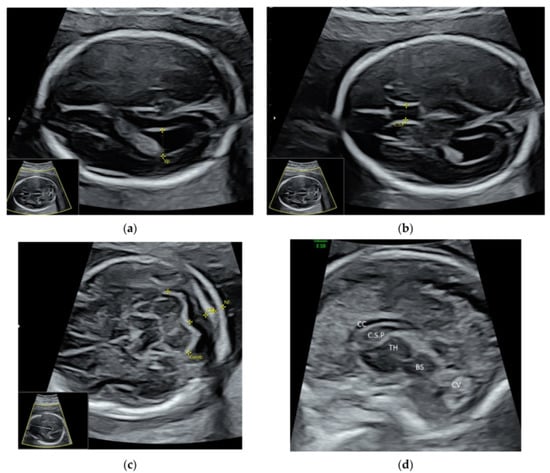

5.1. 3D Neurosonography